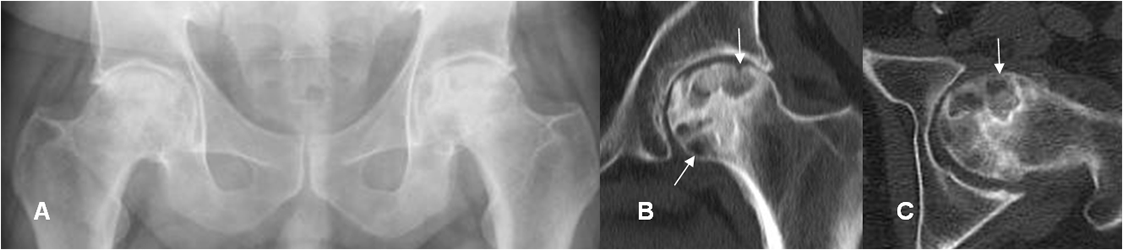

Fig 84 A. Osteonecrosis. Clase D.

A: Rx AP. Aumento de la densidad en la parte superior de las cabezas femorales, por osteonecrosis. Adicionalmente hay prominencia de los bordes laterales de las cabezas femorales, por pinzamiento tipo CAM.

B: TAC reconstrucción coronal y C: TAC axial. Lesiones geográficas en las cabezas femorales, de bordes escleróticos, por osteonecrosis.